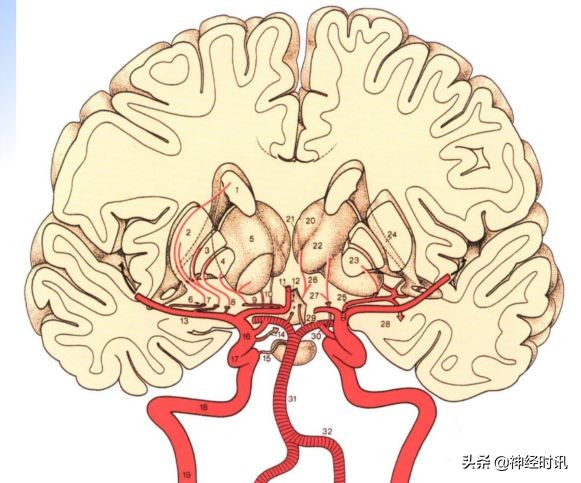

脑的动脉血液供应来自: ① 颈内动脉系统;② 椎-基底动脉系统。

颈内动脉: 颈内动脉经破裂孔进入颅内,颅内段穿硬脑膜经海绵窦,依次分出眼动脉、后交通动脉、脉络膜前动脉、大脑前动脉(视交叉旁分出),终支为大脑中动脉。颈内动脉系统供应:额叶,颞叶、顶叶和基底核等大脑前3/5的血流,又称脑的前循环。

椎-基底动脉系统: 双侧椎动脉入颅后分出小脑后下动脉,行至桥延沟汇合成基底动脉,依次分出小脑前下动脉、脑桥支、内听动脉、小脑上动脉,至脚间窝基底动脉分成左右两条大脑后动脉。

两条大脑后动脉向上呈环状,并发出多支丘脑穿通支、丘脑膝状体穿通支和脉络膜后动脉,皮层支供应大脑颞叶底面和枕叶。

椎基底动脉系统供应脑后部2/5,包括脑干、小脑、大脑半球后部以及部分间脑的血液,又称脑的后循环。

脑出血易发生出血的动脉有: (详情可见下图所示)

•1.大脑中动脉分支→豆纹动脉外侧支

•2.大脑后动脉的分支→丘脑穿通动脉

•3.大脑后动脉的分支→丘脑膝状动脉

•4.桥脑出血是基底动脉分支→旁正中动脉

•5.小脑出血→小脑上动脉分支

•6.脑室出血→脉络丛血管破裂